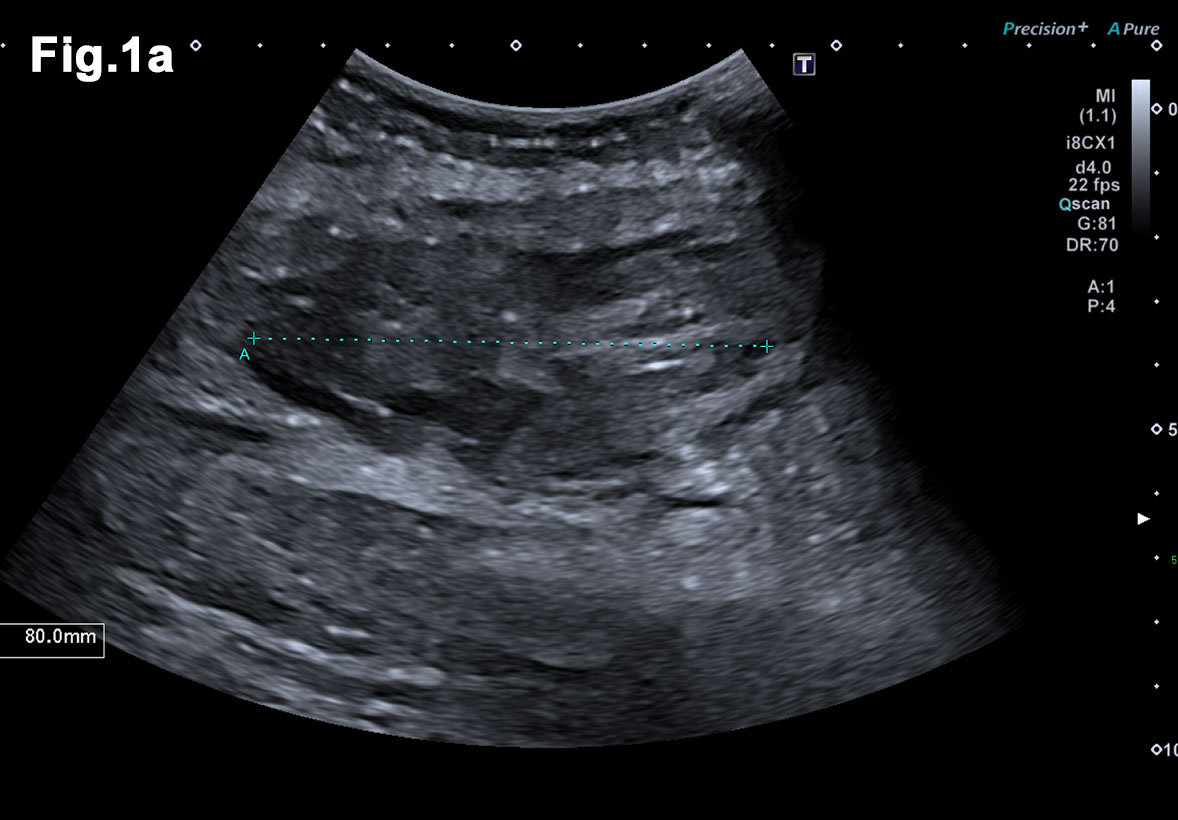

Figure 5 – New presentation of left calf pain with clinical suspicion of a deep venous thrombosis(DVT) – US demonstrated a well-defined hypoechoic mass lesion (a)with moderate vascularity (b) in left gastrocnemius. - Hypoechoic lesion in L gastrocnemius (Fig 5a) - Vascularity demonstrated on Microflow Imaging. (Fig 5b)

- Recent Ultrasound 2018 (Figure 5)

- There was an irregular mass in the left gastrocnemius at the site of tenderness. It was moderately vascular and was subsequently biopsied to reveal a new metastatic deposit similar to the previous lesions and thus disease progression.